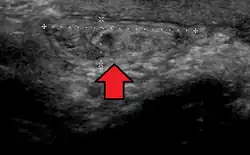

Ultrassom mostrando hérnia inguinal

De longe, as hérnias mais comuns (até 75% de todas as hérnias abdominais) são as chamadas hérnias inguinais. As hérnias inguinais são ainda divididas na hérnia inguinal indireta mais comum (2/3, representada aqui), na qual o canal inguinal é inserido através de uma fraqueza congênita em sua entrada (o anel inguinal interno) e o tipo de hérnia inguinal direta (1/3), onde o conteúdo da hérnia passa por um ponto fraco na parede traseira do canal inguinal. As hérnias inguinais são o tipo mais comum de hérnia em homens e mulheres. Em alguns casos selecionados, eles podem exigir cirurgia. Há casos especiais em que a hérnia pode conter hérnia direta e indireta simultaneamente hérnia pantalonariana, ou, embora muito rara, pode conter hérnias indiretas simultâneas.[15]